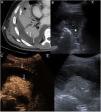

We report the case of a 61-year-old man diagnosed with right basal pneumonia and parapneumonic effusion requiring pleural drainage. Due to his poor clinical course and the low drainage yield, a chest CT was performed, which showed significant pleural effusion with regular parietal pleural enhancement suggesting exudate (Fig. 1A). A chest ultrasound with 2.4 ml contrast agent was performed to complete the study (Sonovue, Rovi, Spain). Ultrasound showed a pleural effusion with countless echoes and internal septa, but no separate loculation (Fig. 1B and C). Following administration of the ultrasound contrast agent, a pattern of enhancement consistent with the known pneumonia and hyperenhancing thickening of the pleural layers were observed, which, together with the ultrasound appearance of the fluid, suggested empyema.

(A–C) Bacterial pleural empyema. (A) CT axial image showing pleural effusion with thickening and hyperenhancement of pleural layers (white arrows) consistent with the split pleura sign. (B) Chest ultrasound showing multiple echoes and septa in pleural fluid, with no obvious loculations (asterisk), findings not visible on previous CT. (C) Chest contrast-enhanced ultrasound. The image on the left shows the contrast-enhanced ultrasound scan, 70 s after administration, and the image on the right shows the standard procedure. The contrast-enhanced image shows thickening and hyperenhancement of the parietal and visceral pleural layers (white arrows), that can be superimposed on those seen in Figure A.

Contrast-enhanced ultrasound has proven to be useful in multiple diseases.1 The split pleura sign consists of hyperenhancing thickening of the visceral and parietal layers of the pleura, separated by a collection of fluid, visualized on intravenous contrast-enhanced CT.2 In our case, contrast-enhanced ultrasound was able to detect this typical CT sign and, together with other findings, led to the diagnosis of suspected empyema.